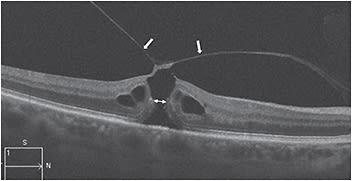

Lamellar holes or partial-thickness macular holes can appear similar to full-thickness macular holes on slit lamp biomicroscopy. OCT imaging of lamellar holes may show an irregular foveal contour or loss of the inner retina, or both, but an intact photoreceptor layer is always present (Figure 4). FTMHs are defined as an absence of all retinal layers in the foveal region (Figure 5, page 40). They can be small (250 µm or smaller), medium (250 µm to 400 µm) or large (400 µm or larger).

Figure 5: OCT shows a small FTMH (225 µm) with focal VMT. The posterior vitreous cortex (arrows) and aperture at which the width of the macular hole is measured (double arrowhead) are visible.